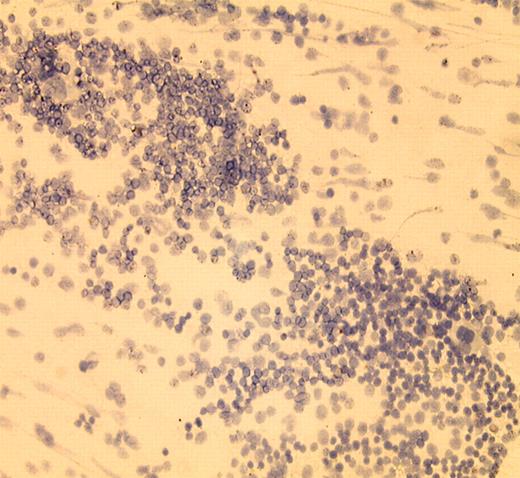

Several orally bioavailable small molecules (ie, PKC412,3 MLN 578,4 and CEP-7015 ) that inhibit activated FLT3 are being evaluated for safety and clinical efficacy in patients with AML whose blasts contain such a FLT3 mutation. Early results suggest that each of these agents has biologic activity in mutant FLT3 AML. In some patients the peripheral blast count decreases, and in a small number the degree of marrow leukemia infiltration declines. Of the first 20 patients with mutant FLT3 AML who received PKC-412, 7 had at least 2-log reduction in the peripheral blast count (1 of whom essentially achieved complete remission [CR]).3 Of 14 similar patients receiving an adequate dose of CEP-701, 5 experienced a reduction in the blast count, albeit for less than 3 months.5 In both trials, ancillary studies documented target inhibition insofar as FLT3 autophosphorylation was decreased. However, since each FLT3 inhibitor also affects other kinases, it is not possible to conclusively link response to FLT3 inhibition, allowing for the possibility that inhibition of other targets could be important.FIG1

In vivo therapeutic effect of IMC-EB10 in EOL-1 xenograft and BaF3-ITD leukemia models. See the complete figure in the article beginning on page 1137.

Signaling via FLT3 is probably important in maintaining the leukemogeneic state in the one-third of AMLs that harbor a FLT3 mutation and could be relevant even in the remainder of cases, most of which at least express this molecule. Interruption of such signaling either by small molecules or with a neutralizing antibody, as accomplished by investigators at Im-Clone Systems (Li and colleagues), may be a therapeutic avenue. The human IMC-EB10 antibody binds to FLT3 and prevents FLT3 ligand–mediated signaling in wild-type cells and autonomous FLT3-mediated signaling in mutant FLT3 leukemia cells. This effect was translated into antileukemia efficacy and a survival benefit in both FLT3-dependent and -independent murine leukemias. It remains unclear why this agent would suppress leukemias that do not clearly depend on FLT3 activation for growth. Nonetheless, taken together these studies provide hope that targeting FLT3 in AML could yield a bountiful harvest of therapeutic success.